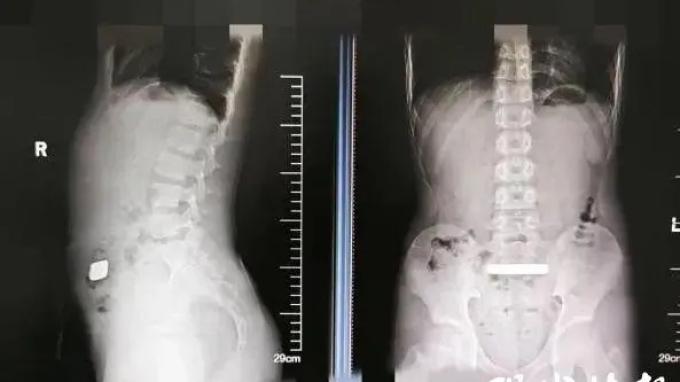

Setelah dilakukan pemeriksaan sinar-X, dokter menemukan benda logam berdensitas tinggi di saluran usus bocah tersebut.

Dengan hasil rontgen lanjutan menunjukkan bahwa emas batangan masih berada di dalam tubuh bocah tersebut, dokter mulai khawatir tentang risiko penyumbatan atau perforasi pada saluran ususnya.